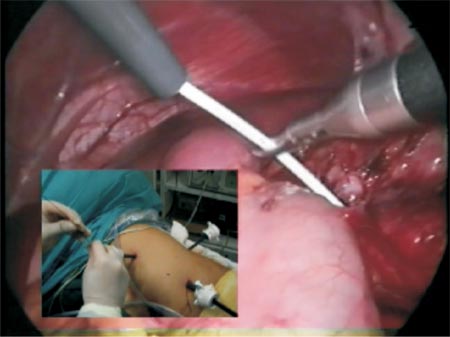

Then, the patient is placed in dorsal decubitus position (45o). The catheters are placed on the abdomen and after the asepsis and antisepsis of the operative field it will be inserted (Photo 2).

Photo 2 - Detail of the tip of the ureteral catheter where a saline solution will be injected and a guidewire will be inserted.

Transperitoneal access was used; however, retroperitoneal access is also feasible. The intra-ureteral catheter facilitates its identification (Figure 2 and Photo 3). The ureter is traced cephalad toward the renal pelvis. NS (normal saline) 0,9% can also be injected through Levine catheter to distend even more the renal pelvis facilitating its identification (Figure 3 and 4). A 3.0 long straight needle could be passed percutaneously or not to lift the pelvis and therefore saving a trocar (Photo 4).

Photo 3 - Hard consistency of the ureter due to indwelling catheter.